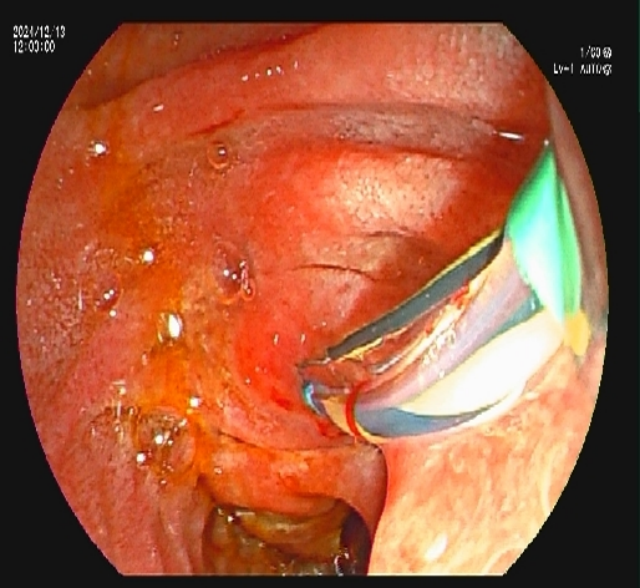

内镜下胰管支架植入术

经全科讨论后,决定为游大爷实施内镜下胰管支架植入术。李春桃主治医师向游大爷及其家属讲解了相关病情及治疗方案,取得同意后在全麻下为其实施了内镜下十二指肠乳头肌切开术(ECT)+内镜逆行胰胆管造影(ERCP)+胰管支架植入术。

术后第二天,游大爷复查血淀粉酶及脂肪酶均正常,可以正常进食稀饭,不再恶心呕吐,可以四处活动。术后五天,复查腹部CT,见胰头部囊肿明显缩小,游大爷开心地说:“我已经不痛了,吃东西也好多了,没想到手术恢复这么快,解决了我11年的病痛!”